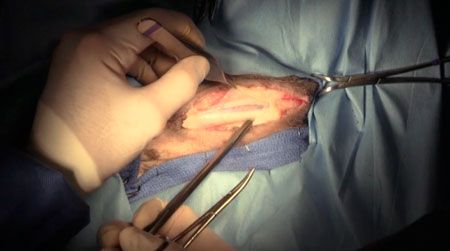

See how one cat diagnosed with this syndrome was successfully treated.